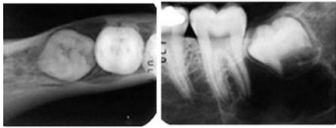

Observe a radiografia a seguir.

Qual das alternativas a seguir descreve o nome da técnica utilizada na imagem de radiografia, para a localização, vestíbulo-lingual de terceiros molares inclusos? É a técnica